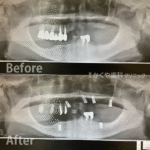

インプラント治療例(80代 女性)_0005

インプラント治療例 「噛み合わせられない/入れ歯が合わない」ということでご来院いただきました。インプラント治療で快適に噛めるようになりました。下顎はロケーターアタッチメント使用しています。 レントゲン画像 実際の見た目の […]